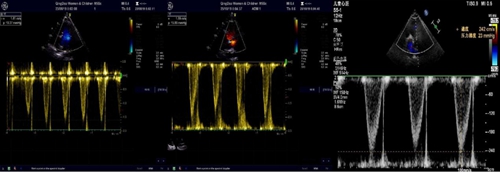

術(shù)后超聲心動(dòng)圖示瓣膜位置固定,無瓣周漏和肺動(dòng)脈瓣反流